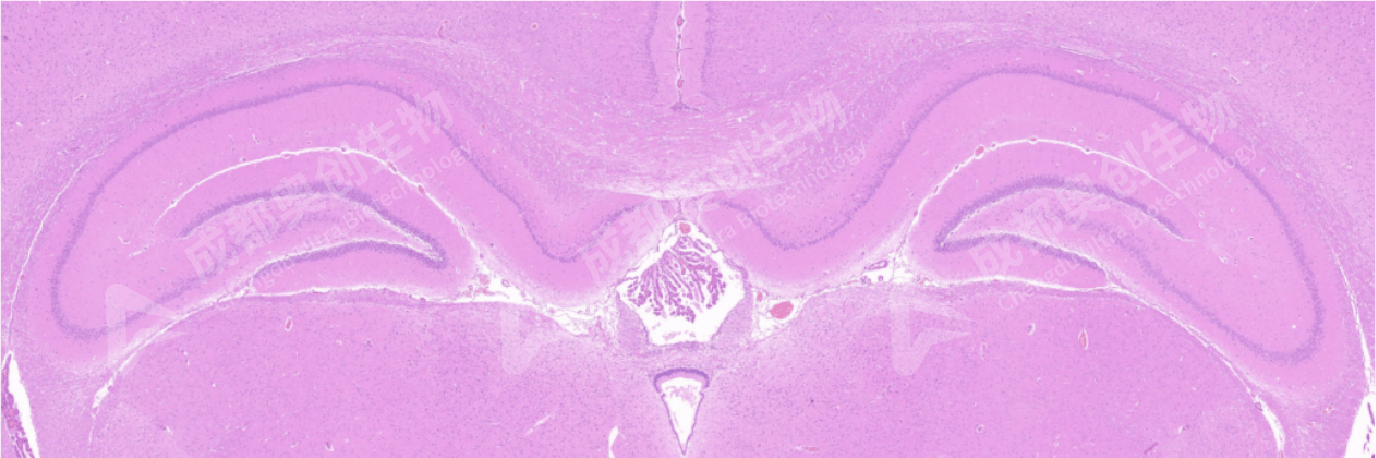

2.大脑海马:

海马(H)是大脑发育过程中较保守的区域。研究表明,其细胞分子机理是依赖于海马突触可塑性。海马根据细胞形态分为CA1、CA2、CA3、CA4区,通常情况下术语上的“海马结构”指的是齿回状和CA1~CA3部位,以及脑脚下。一般组织图片上多显示前3个区。

大鼠海马CA1区,大鼠海马CA2区;

COR/皮质、MED/髓质、H/海马、DG/齿回状、DIC/间脑、N/神经元、NC/胶质细胞、BV/血管。